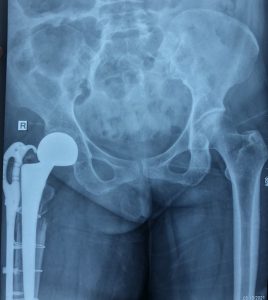

PHẪU THUẬT BẮT VÍT GIA CỐ LẠI KHỚP HÁNG NHÂN TẠO

Bệnh nhân N.T.S., 59 tuổi, ngụ Huyện Tân Châu, Tỉnh Tây Ninh nhập viện trong tình trạng đau nhiều vùng háng phải. Được biết bệnh nhân bị trượt té tại nhà, sau đó bị đau nhiều vùng đùi và háng phải, được người nhà đưa vào khám ở bệnh viện địa phương và được chuyển vào cấp cứu tại Bệnh viện Xuyên Tây Ninh.